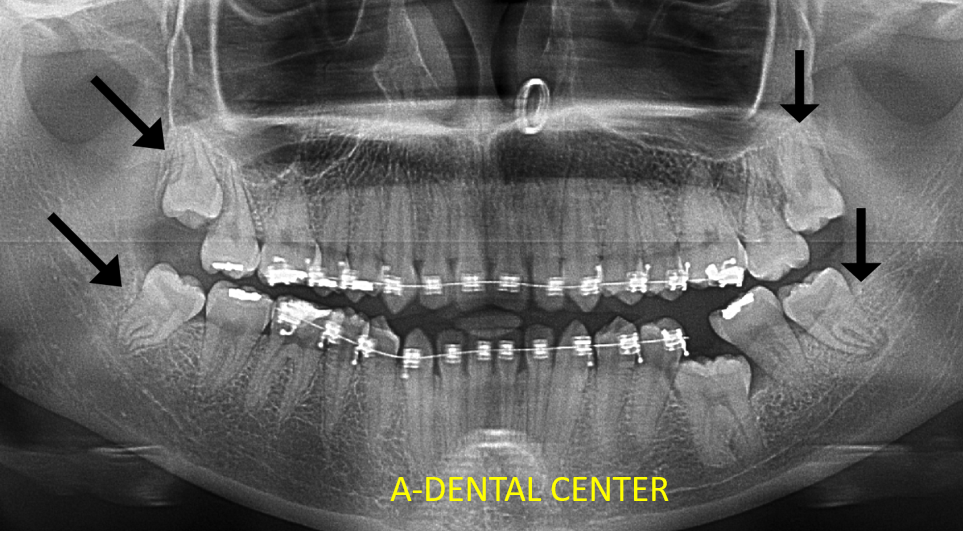

Dental X-rays in North Hollywood reveal what clinical examination simply cannot. They show several critical things that would otherwise go completely undetected:

- Impacted, unerupted, or problematic wisdom teeth — often completely asymptomatic until they cause damage to adjacent teeth

- Infections or cysts at the root tips of teeth — detectable only through imaging

- Root fractures and other structural issues — frequently missed without X-ray confirmation